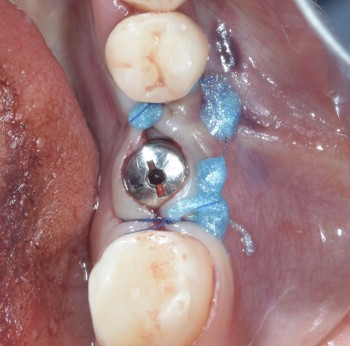

2 работы в портфолио